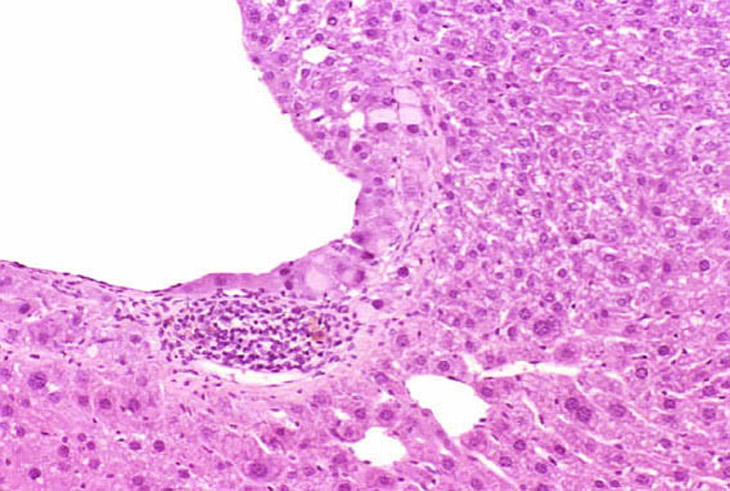

In some foci of cellular alteration, primarily basophilic foci, hepatocytes may occasional be seen to protrude into the lumen of hepatic veins. They are usually lined by a layer of flattened endothelial cells. This change has been considered by some to represent a form of microinvasion and such lesions have been diagnosed as hepatocellular carcinomas, possibly motivated by the fact that most are seen within foci induced by treatment with hepatocarcinogens. However, similar changes are occasionally seen in untreated mice and may not necessarily be associated with a focus of cellular alteration. Consequently, we cannot be certain that this change is actually a microcarcinoma. Two clusters of hepatocytes protruding into a large hepatic vein.

Another example of protrusion of hepatocytes into an hepatic vein.